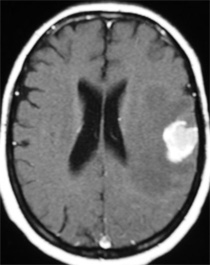

CASO 2 :Tratamiento de Metástasis de Cáncer de Pulmon con Radiocirugía Estereotáxica

Joven profesional con cáncer de pulmón y metástasis recurrente después de tratamiento en el extranjero. La resonancia magnética muestra al tumor rodeado de edema cerebral. El paciente presenta cefalea, convulsiones y trastornos del campo visual